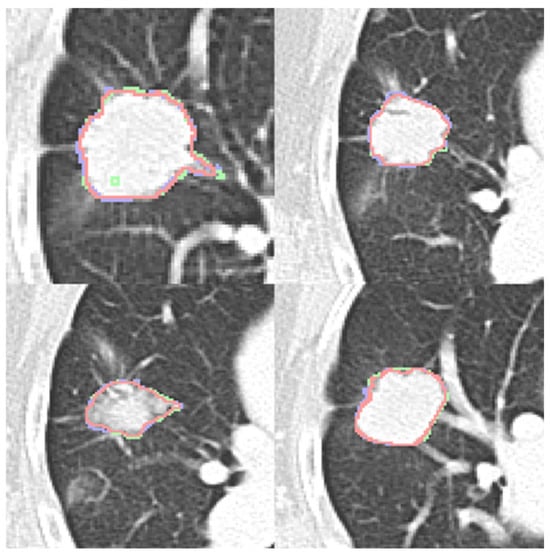

In addition to standardized lateral cephalometric radiographs, comprehensive assessment using dental cone-beam computed tomography (CBCT) and CT has become commonplace in the diagnosis and treatment of jaw deformities. Simulation based on cephalometr...